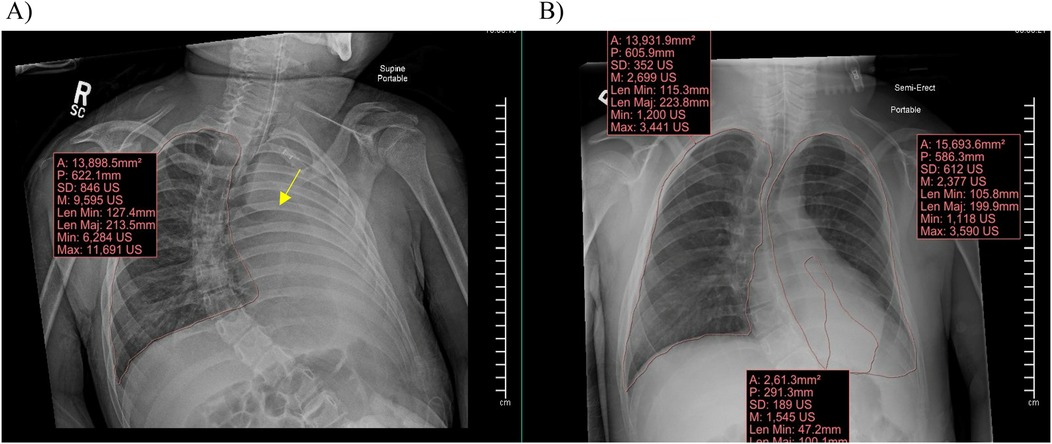

Information obtained included subjects’ demographic information (age, ethnicity, race, gender), height (cm), weight (kg), PICU length of stay (LOS) in days, cause of the RLD, and the admission diagnosis for which respiratory support was required. We collected chest x-rays for each patient upon admission to the PICU, prior to initiation of APRV (T0), and at times closest to 24 h (T1) and 48 h (T2) of APRV. The volume of atelectasis was calculated as a percentage of relative volumetric total lung volume by measuring the segmented atelectatic lung surface area (mm2) as compared to the total surface area of the expanded lung in each patient utilizing a region of interest (ROI) volume tool tracing with the AP portable chest radiographs at each time point for each encounter in the study. The volume of the fully expanded lung for each patient was calculated from the contralateral lung diaphragmatic excursion if there was not atelectasis or infiltrate and from prior chest radiographs in the case of bilateral involvement. All segmentation and calculations were performed by an experienced pediatric radiologist with 22 years of experience using Synapse PACS, FUJIFILM Inc. Lexington, MA, USA Figure 2. We documented ventilator settings including positive end-expiratory pressure (PEEP), inspired supplemental oxygen concentration (FiO2), and mean airway pressure (Paw) in children while on conventional ventilation, and maximum pressure delivered (Phigh), FiO2, and Paw in children receiving APRV. We recorded measurements of gas exchange, including partial pressures of oxygen and carbon dioxide (PaO2 and PaCO2) on arterial or venous blood gases, and utilized this information along with ventilator settings to calculate each child's Horowitz Index for Lung Function (P/F ratio) and oxygenation index (OI), to more accurately compare gas exchange while accounting for differences in patient size. We used oxygen saturation as measured by pulse oximetry (SpO2) as a substitute to calculate SpO2/F ratio and oxygenation saturation index (OSI) when arterial blood sampling was not available. Length of mechanical ventilation was collected, defined as the time from initiation of APRV to extubation in hours. We collected data regarding use of neuromuscular blockade, prone positioning, and receipt of bronchoscopy. We also described any documented complications while on APRV which could be attributed to this ventilation mode, primarily air leak syndrome or clinically significant hypotension requiring initiation of vasopressors.

Figure 2. Synapse PACS system and the volume calculation tool used to calculate total lung surface area and area of atelectasis. (A) Demonstrates a clear fully expanded right lung with complete atelectasis of the left lung with abrupt cut off of the left mainstem bronchus (arrow). (B) Demonstrates a clear fully expanded right lung with partial atelectasis of the left lung with volumes demonstrated for quantification at each time point.